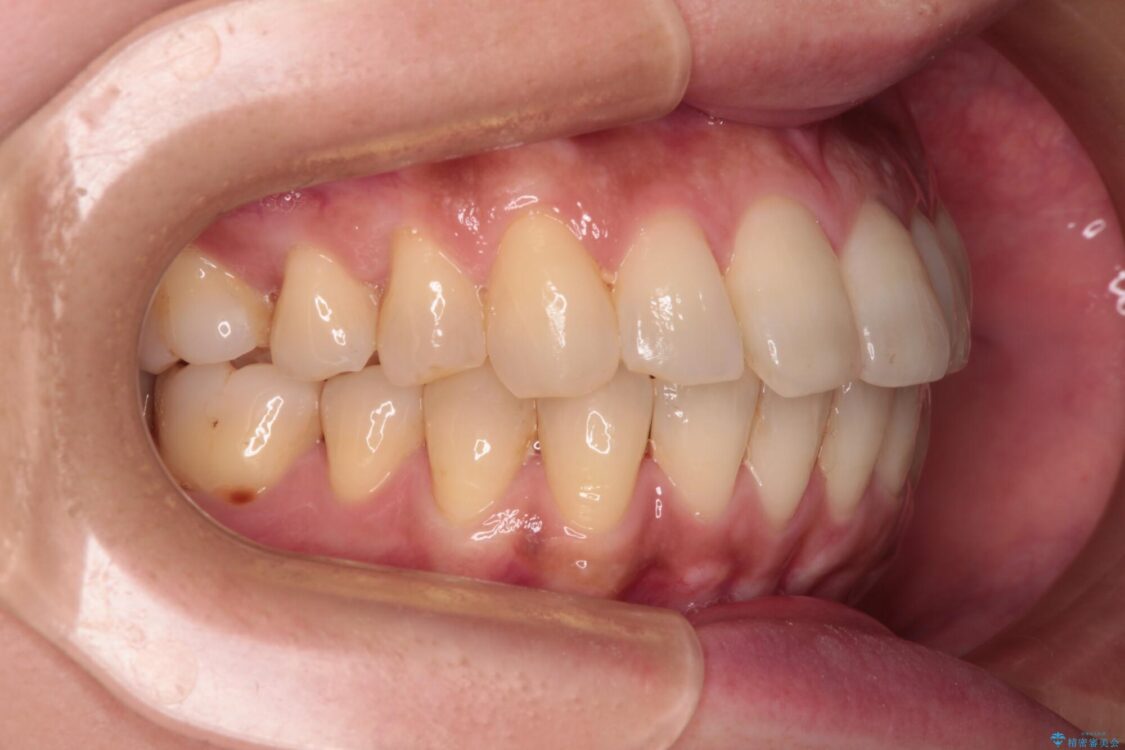

治療前

• インビザラインによる矯正治療と奥歯のインプラント治療 治療前画像